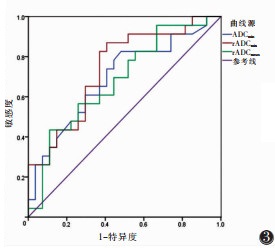

绘制ADCmin、rADCmin、rADCmean预测直肠癌区域淋巴结转移的ROC曲线,得出诊断转移淋巴结最佳界值分别为0.525×10-3 mm2/s、0.410、0.657,其AUC分别为0.692、0.738、0.681(图 3),敏感度为43.5%~82.6%,特异度为51.9%~88.9%。

| 图 3 ADCmin、rADCmin、rADCmean分别预测区域转移淋巴结的ROC曲线 |

采用logistic回归分析及ROC曲线分析ADCmin、rADCmin、rADCmean联合对直肠癌淋巴结转移的预测效能,AUC为0.692~0.738(图 4),敏感度为82.6%~87.0%,特异度为51.9%~59.3%。

| 注:其中ADCmin+rADCmin、rADCmin+rADCmean、ADCmin+rADCmin+rADCmean预测区域转移淋巴结的ROC曲线(黑色)重叠。 图 4 ADCmin、rADCmin、rADCmean两两联合及三者联合预测区域转移淋巴结的ROC曲线 |